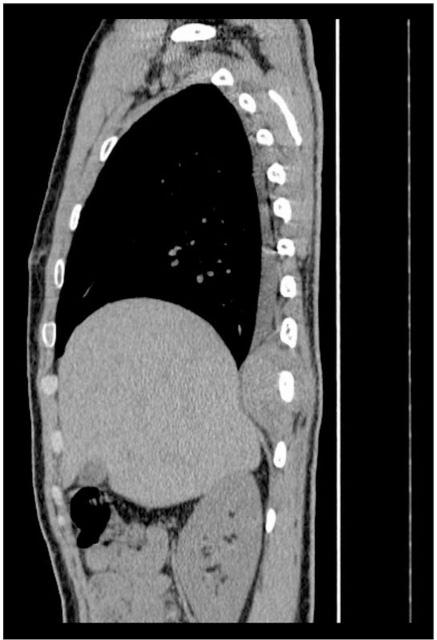

Askin tumor is an uncommon malignant neoplasm in the thoracopulmonary region mainly occurring in children and adolescents. Four young patients with histologically proven Askin tumors were treated in our hospital. In all patients, chest computed tomography imaging demonstrated a chest wall mass with or without destruction of ribs. All patients underwent radical mass resection and postoperative chemotherapy. By the time this article was completed, two of the patients had died with local chest wall recurrences. Here we focus on the imaging features, differential diagnosis, pathology and prognosis of this rare disease.